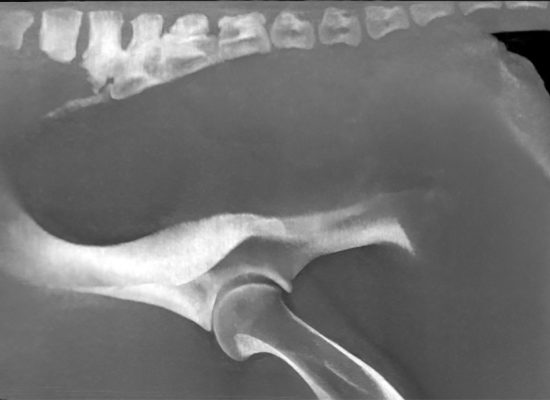

1- Examen de la tête dans l’exploration des pathologies dentaires et sinusales, des troubles d’encensement (“Head-Shaking”), des voies respiratoires supérieures ou du système nerveux central.

2- Examen de la colonne cervicale, qui peut être complété par une myélographie, dans l’exploration de l’ataxie, de la cervicalgie ou des boiteries antérieures d’origine axiale.